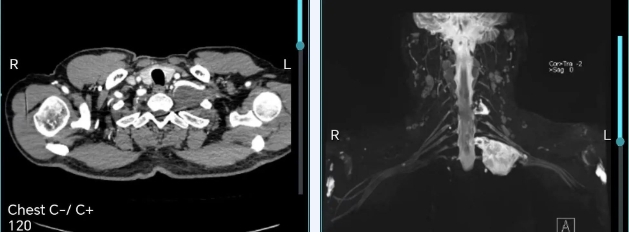

徐全在术前详细评估时指出,纵隔肿瘤首先要看肿瘤性质:该患者完善颈胸部增强CT,判断肿瘤性质为神经鞘瘤可能性大,神经鞘瘤一般为良性,有明显包膜,与周围组织有界限,这给了我们极大信心。其次要看肿瘤位置:肿瘤位于左侧胸廓入口处,上界平第6颈椎,下界为胸膜,内侧为颈椎椎体并有部分肿瘤进入C7椎间孔,前方锁骨下动脉受挤压走行迂曲,后方脊神经根穿行其中,界限不清。处处都是危险区域,为了避免损伤脊神经根及臂丛,根据肿瘤性质,我们分析可能可以采取包膜内切除的方法。最后要确定手术入路,胸廓入口处肿瘤通常位于锁骨下方,要充分暴露术野,一般采用颈部胸部联合的L形切口。

术中取左颈胸部L形切口,充分暴露锁骨下方区域。再依次游离锁骨下静脉、颈内静脉、锁骨下动脉、颈总动脉、迷走神经、胸导管,一一牵拉开,充分显露肿瘤。见肿瘤质地较软,有完整包膜,大小约5*4*4cm,考虑与术前评估相符,为神经鞘瘤。因此按照术前计划,将肿瘤外层包膜打开,将内层肿瘤整体剥除。